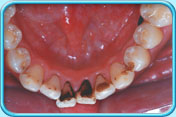

有黑色漬的牙齒經常吸煙或飲用深色的飲品如茶、咖啡等,色素就會沉積在牙齒表面。

噴粉潔牙情形

清除黑色漬後的牙齒戒煙及減少飲用深色的飲品以減少色素積聚。